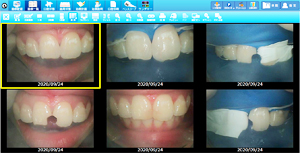

• ラバーダムを使用した治療画像